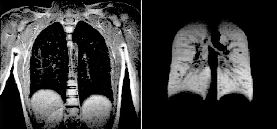

Una imagen de resonancia magnética (IRM) de los pulmones de un sujeto normal (izquierda), y otra de pulmones normales hecha después de que una persona inhalara gases de helio hiperpolarizado (derecha), fueron dadas a conocer por la Universidad de Virginia. Las técnicas de scaner como la IRM iluminan partes del cuerpo pero no muestran algunos órganos adecuadamente. Ahora los científicos exploran una nueva manera de observar dentro del organismo de los pacientes, pues mientras el helio llena los pulmones éstos se iluminan, lo que permitiría a los doctores observar cómo pasa el aire respirado a través de dichos órganos Ť Foto: Ap